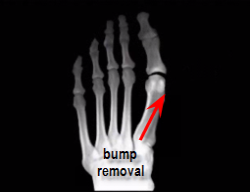

The most common and probably also the simplest way to correct a hallux limitus deformity is to "just" remove the bone spur on the top of the foot that is causing limitation of motion of the big toe joint and accompanying pain.

The bone spur on top of the foot may be growing either from the head of the first metatarsal or from the base of proximal phalanx (toe), or from both bones. In many instances the bone spur, if large enough will have fractured and the fractured piece of bone must be removed as well.